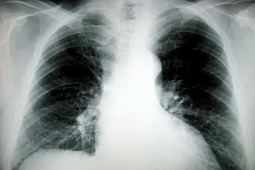

Przewlekła obturacyjna choroba płuc jest jednym z najczęściej występujących schorzeń dróg oddechowych. Mimo to wciąż niewiele osób potrafi rozszyfrować skrót POChP, oznaczający chorobę będącą połączeniem rozedmy płuc i przewlekłego zapalenia oskrzeli, prowadzącą nieuchronnie do systematycznego zmniejszania się pojemności płuc.

Podstawowym objawem POChP jest przewlekły kaszel i odkrztuszanie wydzieliny. Wciąż pokutuje opinia, że „poranny kaszel palacza” czy występująca w czasie wysiłku zadyszka to zjawiska normalne i typowe dla ludzi palących papierosy, zwłaszcza po 40. roku życia. Dlatego POChP wykrywane jest późno, gdy dochodzi do poważnego upośledzenia pracy układu oddechowego i powikłań w postaci chorób sercowo-naczyniowych bądź raka płuca. Osoby, które obserwują u siebie przewlekły kaszel i odkrztuszanie, zwłaszcza, jeśli są wieloletnimi palaczami, powinny zgłosić się do lekarza i poprosić o skierowanie na badanie spirometryczne. Spirometria to badanie proste i nieinwazyjne. Pozwala ocenić objętość i pojemność płuc oraz przepływy powietrza w oskrzelach i płucach. Jest zalecane przez Polskie Towarzystwo Chorób Płuc oraz Światową Inicjatywę Zwalczania POChP (GOLD), która jest koordynatorem obchodów Światowego Dnia POChP.